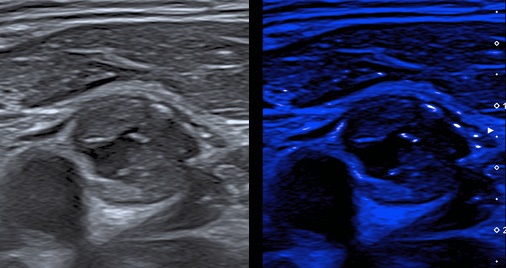

Рис. 4. Ультразвуковое изображение АСБ с множественными МК в режиме MicroPure.

Примечание: цветное изображение доступно в электронной версии журнала.